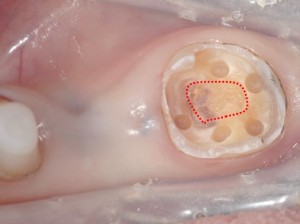

まず周りにホール(穴)を形成します。(下写真:赤点線部分に歯髄がある)